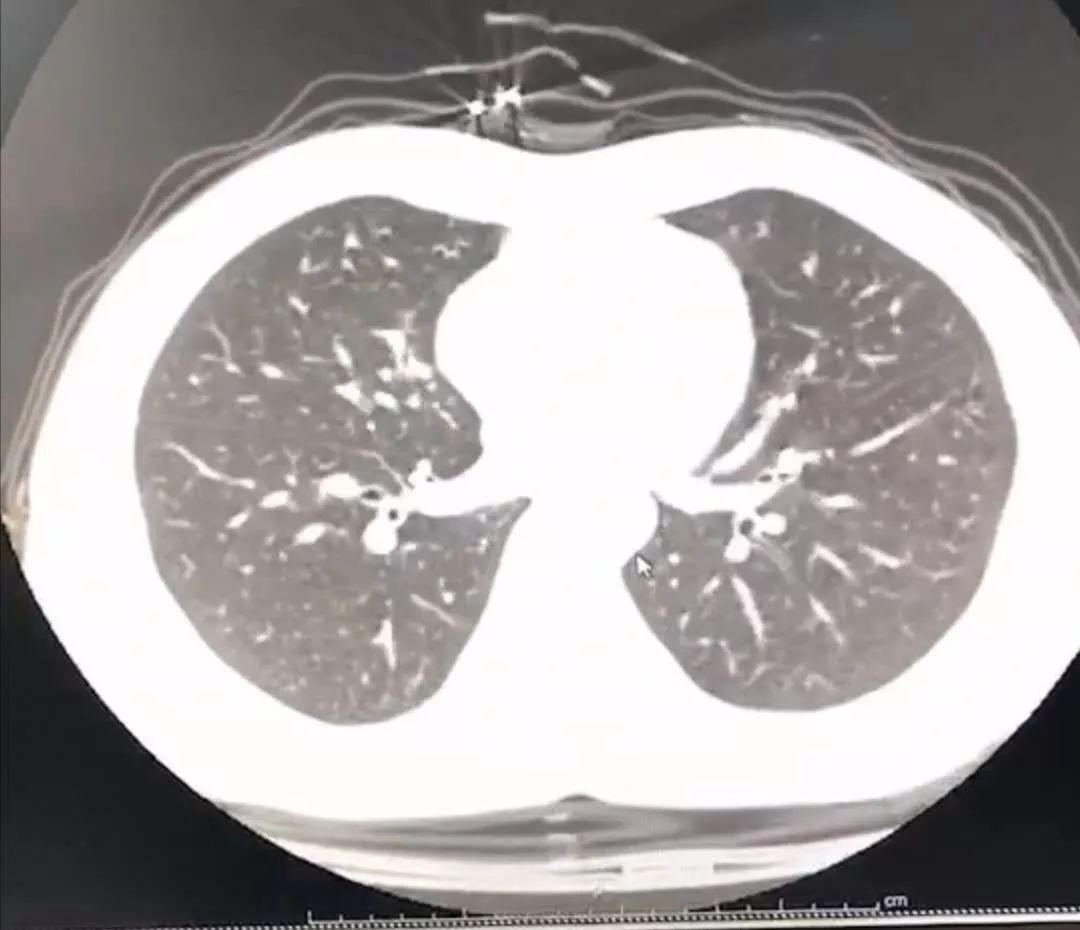

1、具体来说,CT或者X光片的影像就像黑白照片,只有黑、白、灰三种颜色。这些颜色并不代表器官的真实颜色,而是反映了器官不同部位对X线的吸收能力。在正常情况下,肺泡组织中含气量多,肺充分膨胀,X线能够很容易地穿过肺组织,因此在胸片或CT上呈现为黑色。然而,当肺部出现炎症反应时,情况就会发生变化。

2、新冠肺炎的肺部影像在CT或X线上表现为白色。以下是关于新冠肺炎肺部影像颜色的详细解正常肺部与病变肺部的影像对比:正常人的肺部在CT或X线影像上呈现为相对黑色的区域。当肺部出现病变,如新冠肺炎时,X线的穿透力会减弱,导致病变区域在影像上呈现为白色。

3、早期表现早期肺部CT以单发外周肺野磨玻璃影为主,表现为局部肺组织密度轻度增高,但仍可见血管及支气管纹理。此阶段磨玻璃影反映肺泡内渗出性改变,与病毒主要侵犯肺外周组织的特点相关。对于有新冠病毒接触史且出现呼吸道症状者,早期发现磨玻璃影需高度警惕新冠感染可能。

5、新冠感染患者的CT影像表现主要包括以下方面: 肺部磨玻璃影和实变影这是新冠感染最常见的CT表现。磨玻璃影反映肺部炎症,表现为局部肺组织密度轻度增高,呈云雾状;实变影则提示肺泡内充满炎症细胞和渗出物,导致肺组织密度显著增高,类似肺炎表现。二者常同时出现,提示病变进展。

6、新冠肺炎即新型冠状病毒肺炎,患者的肺部影像在CT或X线上表现为白色。肺部阴影是影像学名词,目前造影成像的原理即通过X线穿透组织后打在胶片或底板上形成影像,基本为黑白色。正常人的肺是相对黑色的区域,而肺部出现阴影的情况下,X线的穿透力会减弱,在CT或X线片上会表现为白色影像。